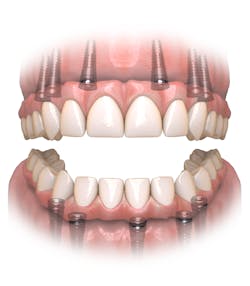

As a prosthodontist who has spent the last 25 years offering full-arch treatment to my patients and teaching the Hybridge full-arch protocols for most of that time, the phrase “Pick a Path” has come to refer to the difficult decision a patient makes to either commit to restoring their natural dentition or to replace their remaining teeth with a completely implant-supported prosthesis, as in a full-arch solution. The last decade has seen this implant modality gain in popularity.

Today, more than ever, patients expect and hope their dental restoration will solve what has historically been a lifetime cycle of dental problems and expense. In this case, a straightforward, conventional restorative treatment plan that focuses on restoring the patient’s natural teeth may not make the most sense long term. After comparing both restorative paths, the full-arch implant option would likely prove to have a better prognosis, lower cost, and require much less time and fewer appointments.